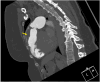

"Cases of SCMR" is a case series on the SCMR website (https://www.scmr.org) for the purpose of education. The cases reflect the clinical presentation, and the use of cardiovascular magnetic resonance (CMR) in the diagnosis and management of cardiovascular disease. The 2022 digital collection of cases are presented in this manuscript.

Keywords: Arrhythmogenic cardiomyopathy; COVID-19; Cardio-oncology; Congenital Heart disease; Coronary artery aneurysm; Hydatid disease; Hypertrophic cardiomyopathy; Metastatic disease; Myocardial. infarction; Myocarditis; Takotsubo; Vaccine associated myocarditis; Viability.